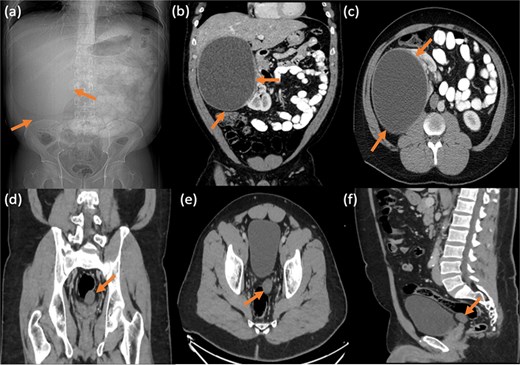

Pelvic magnetic resonance imaging (MRI) further characterized the pelvic lesion as a well-defined, non-enhancing, fluid-filled cyst measuring 3 × 2 × 1 cm without solid components, raising suspicion for pelvic hydatid seeding, although peritoneal inclusion cyst was also considered (Fig. 3). A 99mTc-dimercaptosuccinic acid (DMSA) scan showed preserved renal function with the right kidney contributing 25.7% of total function and a photopenic defect at the cyst site (Fig. 4). No other lesions were found on chest CT or brain MRI. Colonoscopy ruled out malignancy but revealed incidental low-grade adenomas.

Static image of the abdomen at 2 h after IV injection TC-99 m DMSA, showing normal morphology & corticotubular function of the left kidney. Large photopenic area occupying the upper half of the right kidney while its lower half showed preserved cortical function.